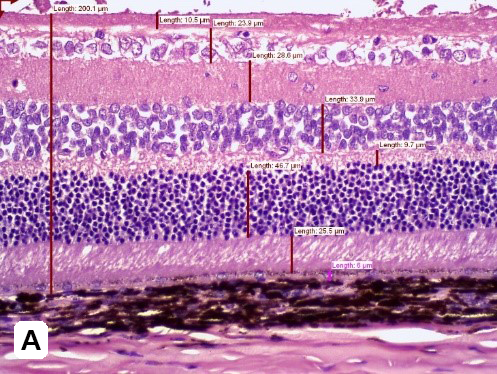

Figure 3: Quantitative image analyses of retinal layers using H&E staining of STZ-induced (A) vs non-induced (B) retina at Day 72 post-induction. An increase in the total thickness of retinal and ONL is found in STZ-induced animals. Magnification 200x)